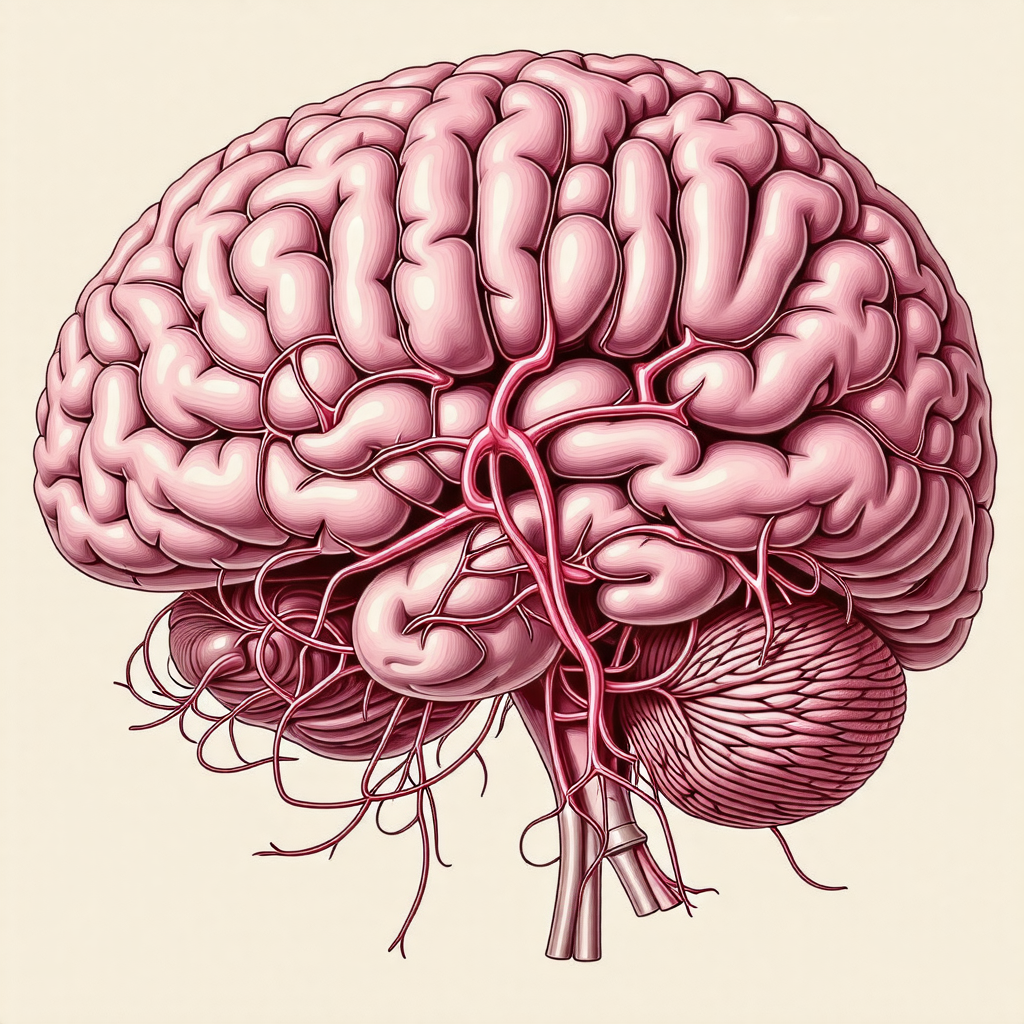

제목: 뇌구조에 대한 이해: 인간의 창조적인 거대한 네트워크 뇌는 인간 및 동물의 중추신경계에서 가장 중요한 역할을 수행하는 기관 중 하나입니다. 이 복잡하고 정교한 기관은 우리의 생각, 감정, 행동을 조절하며, 운동, 기억, 인식, 감각 등 다양한 기능을 수행합니다. 뇌의 각 부분은 특수한 기능을 가지고 있으며, 이 글에서는 뇌의 구조와 각 부분의 역할에 대해 자세히 알아보고자 합니다. 이를 통해 뇌의 놀라운 복잡성과 다재다능함을 이해하고, 더 나아가 뇌의 건강을 유지하는 방법에 대해 생각해 볼 수 있습니다.1. 뇌의 구성1.1 대뇌뇌의 가장 큰 부분인 대뇌는 우리의 지능과 인지능력을 담당합니다. 대뇌는 왼쪽과 오른쪽 두 개의 반구로 나누어지며, 각각의 반구는 서로 다른 기능을 담당합니다. 왼쪽 반구는..